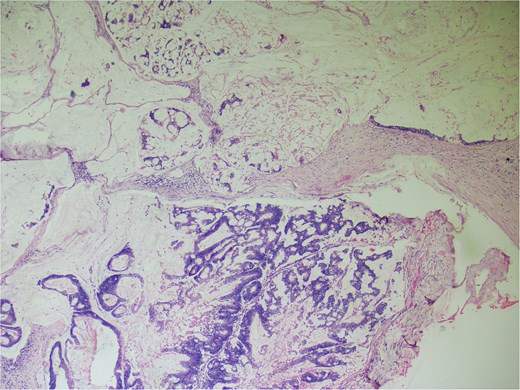

On gross examination, growth seen involving ileocecal junction extending upto caecum measuring 6.5 × 6.0 × 4.3 cm. Cut section showed solid creams white firm to friable areas with mucoid consistency at places. A nodular growth is identified in the attached mesentery measuring 3.5 × 2 × 2 cm. On cut section solid white areas are seen along with focal area showing mucoid consistency. The histopathological report concluded mucinous adenocarcinoma of caecum, pT3N1MX, with evidence of lymphovascular invasion. The tumor invaded through the muscular propria layer (Figs 4 and 5). Additionally, acute appendicitis was found.

Hematoxylin and eosin ×40: Section shows lymph node effacement of by pool of mucin and few atypical cells and the periphery show compressed lymphoid tissue.